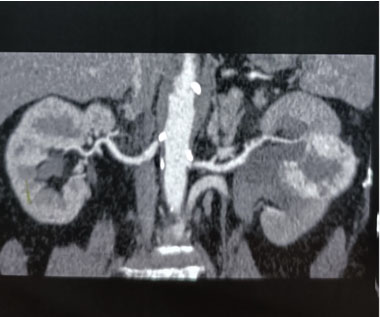

Case Report: We present a female with right perinephric abscess and reno-duodenal fistula secondary to a long-standing history of kidney stones. Treatment involved drainage of the abscess, nephrostomy tube placement, intravenous antibiotics, and open nephrectomy and duodenal repair with gastrojejunostomy.